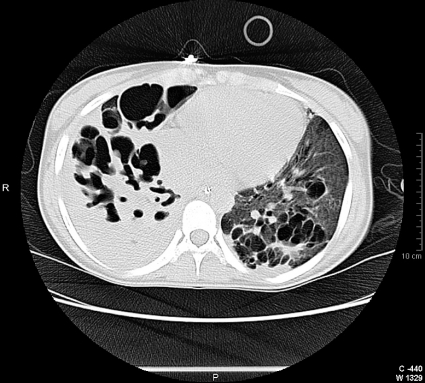

Upprepade lungröntgen- och DT-toraxundersökningar visar att höger lunga är svårt destruerad, och det finns även omfattande parenkymförändringar på vänster sida (Figur 1 och 2). Hon eftervårdades i Halmstad och förbättras långsamt. Vid utskrivning efter 3,5 månader klarade hon att gå några hundra meter men har en kvarstående lungskada med stora emfysemblåsor i höger lunga och kombinerad restriktiv och obstruktiv lungfunktionsinskränkning.